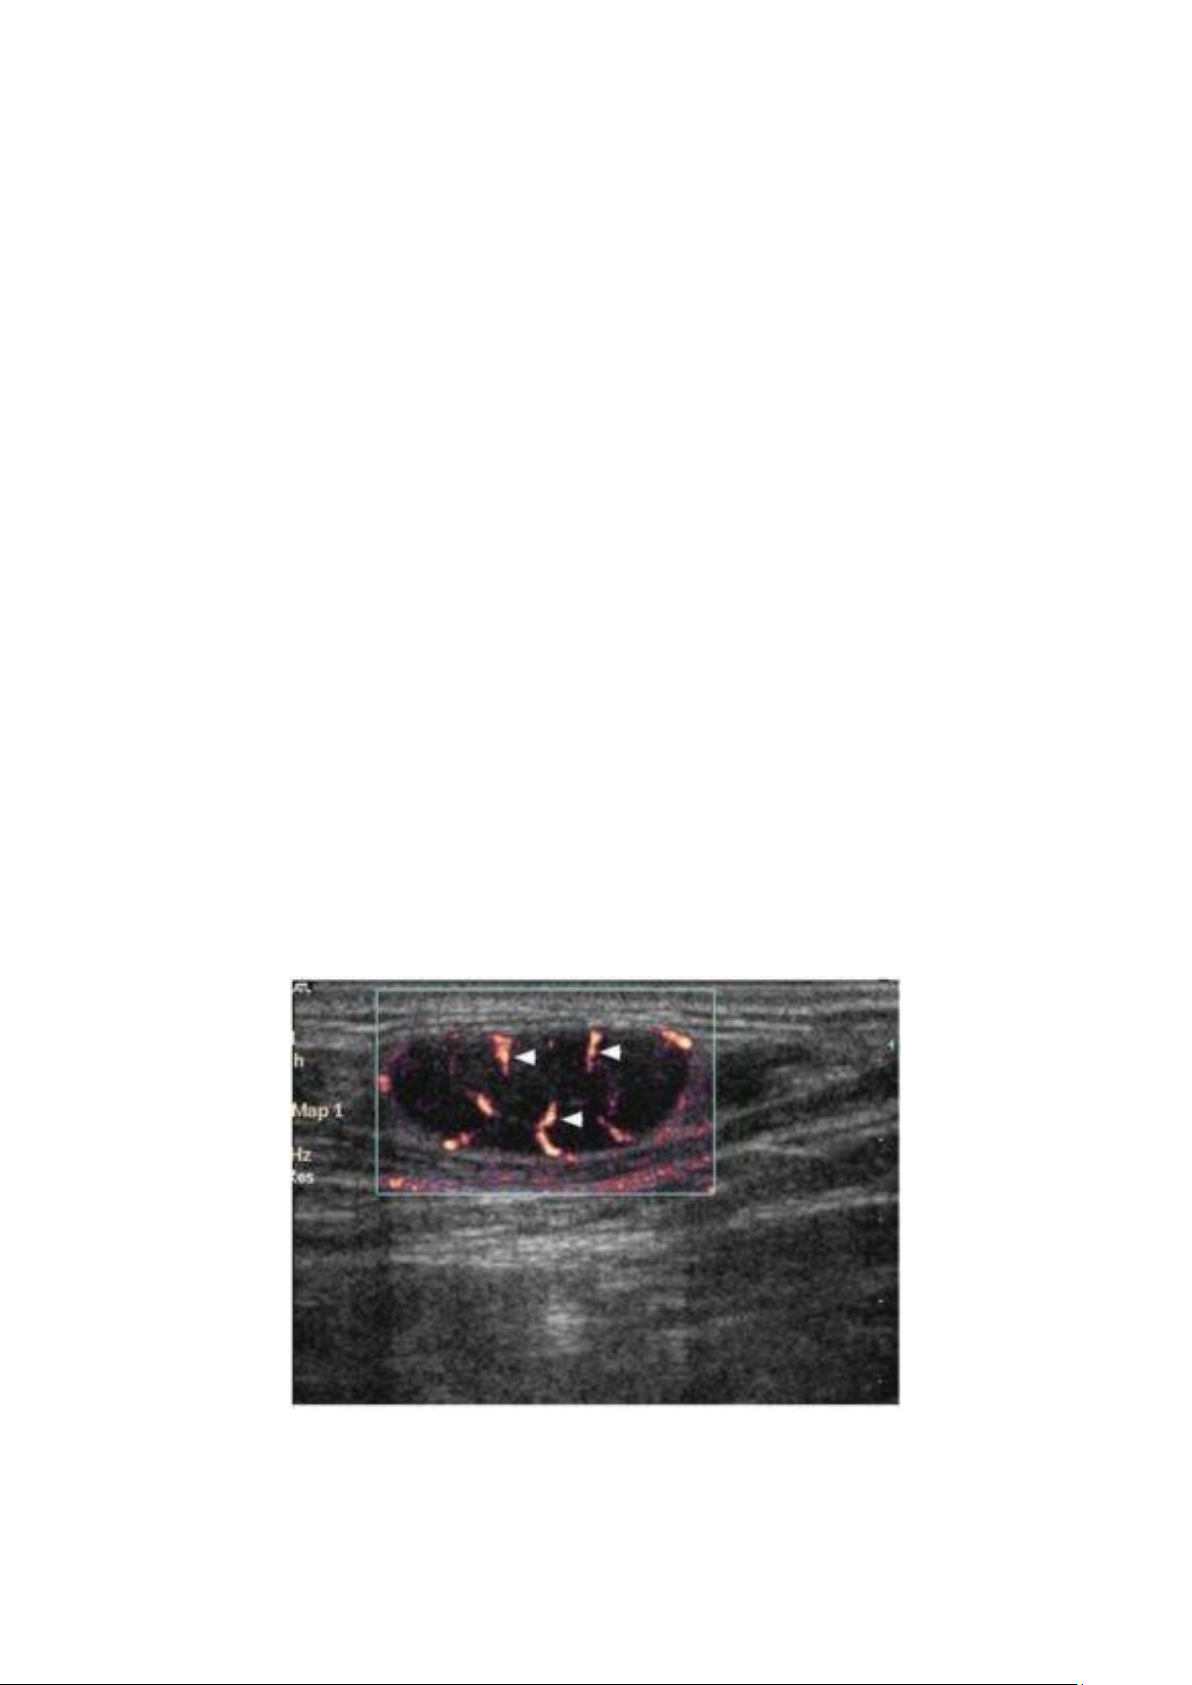

Hình 1.5. Siêu âm Doppler năng lượng của hạch di căn với mạch máu phân bố ngoại biên (đầu mũi tên). lOMoAR cPSD| 46342985 9

Hình 1.6. Hạch nhỏ di căn: a. hạch hình bầu dục, echo kém, mất rốn hạch, bờ rõ, không

phù nề mô xung quanh, tăng sinh mạch máu ở rìa, có 2 vùng không tưới máu (mũi tên). b,c:

đại thể và giải phẫu bệnh tương ứng với 2 vùng di căn.